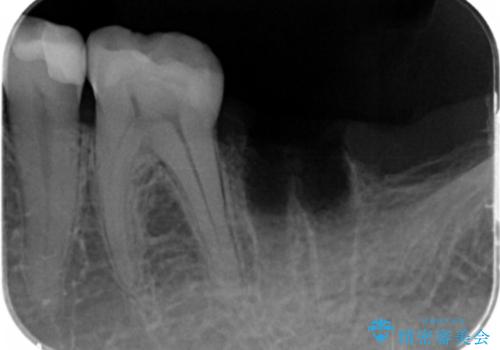

X線検査を行ったところ、セラミッククラウン下に虫歯が再発し、歯の破折も認めました。

X線を撮ることで、外から見てもわからない、歯の問題点をより正確に把握することができます。